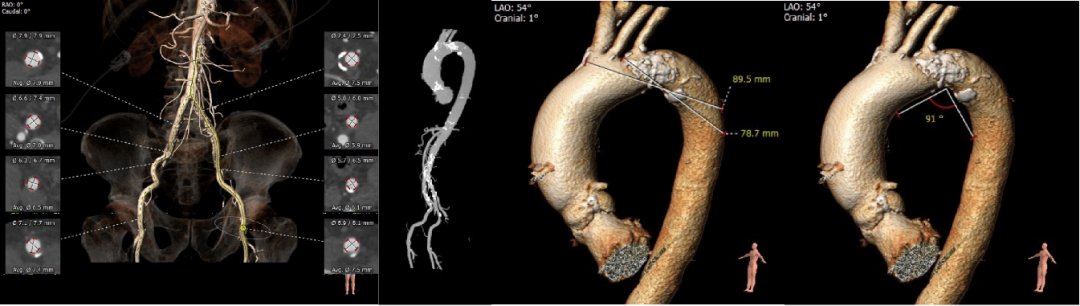

术前CT评估

• Type1型二叶式主动脉瓣,重度钙化,钙化分布稍欠均匀,左右瓣叶融合形成钙化嵴,无瓣叶严重钙化,无冠窦较大;

• 左右冠开口高度可,未见明显冗长瓣叶,冠脉散在钙化;

• 流入段形态呈直桶状,瓦氏窦,窦管交界及升主动脉内径可;

• 主动脉瓣环与水平面夹角可,非横位心,主动脉弓角度与宽度可;

• 入路血管块状散在钙化,双侧股动脉穿刺区域散在钙化,左侧髂外动脉管径稍偏细,右侧入路血管内径尚可;

主动脉根部测量

瓣上结构测量与分析

冠脉阻挡风险及钙化评估

外周血管入路评估